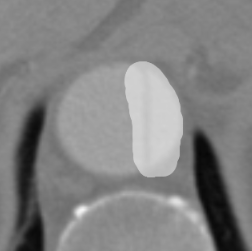

Figure 9 shows axial CTA images of an aortic dissection case. In both rows of this figure an example for executing an inpainting with the inpainting tool is given. The image section of all sub-figures is equal to the defined region of interest. The sub-figures in Figure 9 show from left to right: unedited CTA scan showing the aorta and surroundings, the mask used for the inpainting and the inpainting result. The Sub-images (a) and (b) include a dissected aorta, whereas the dissection is removed in the sub-images (d) and (f).

(b) Masked image

(c) Inpainting result

Figure 9: Two examples for an inpainting of an aortic dissection utilizing the inpainting tool.

Looking at the results presented in Figure 9, one can see that the depicted dissected aorta is successfully changed to a healthy looking aorta. But it is also noticeable, that the region reconstructed by the inpainting is slightly blurred, which could be addressed by refinement of the EdgeConnect model. The timing analysis in section 6 shows that a call of the inpainting tool is completing in around four seconds, wherein the majority is caused by executing the neural network. This indicates the code of the inpainting tool itself offers little room for speeding up the application.